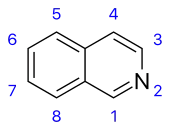

Isoquinoline derivatives and related alkaloids [82]

Simple derivatives of isoquinoline [83] | Tyrosine or phenylalanine → dopamine or tyramine (for alkaloids Amarillis) [84][85] | Salsoline, lophocerine [82][83] |

| Derivatives of 1- and 3-isoquinolines [86] | N-methylcoridaldine, noroxyhydrastinine [86] | ||

| Derivatives of 1- and 4-phenyltetrahydroisoquinolines [83] | Cryptostilin [83][87] | ||

| Derivatives of 5-naftil-isoquinoline [88] | Ancistrocladine [88] | ||

| Derivatives of 1- and 2-benzyl-izoquinolines [89] | Papaverine, laudanosine, sendaverine | ||

| Cularine group[90] | Cularine, yagonine [90] | ||

| Pavines and isopavines [91] | Argemonine, amurensine[91] | ||

| Benzopyrrocolines [92] | Cryptaustoline [83] | ||

| Protoberberines [83] | Berberine, canadine, ophiocarpine, mecambridine, corydaline [93] | ||

| Phthalidisoquinolines [83] | Hydrastine, narcotine (Noscapine) [94] | ||

| Spirobenzylisoquinolines [83] | Fumaricine [91] | ||

| Ipecacuanha alkaloids[95] | Emetine, protoemetine, ipecoside [95] | ||

| Benzophenanthridines [83] | Sanguinarine, oxynitidine, corynoloxine [96] | ||

| Aporphines [83] | Glaucine, coridine, liriodenine [97] | ||

| Proaporphines [83] | Pronuciferine, glaziovine [83][92] | ||

| Homoaporphines [98] | Kreysiginine, multifloramine [98] | ||

| Homoproaporphines [98] | Bulbocodine [90] | ||

| Morphines[99] | Morphine, codeine, thebaine, sinomenine[100] | ||

| Homomorphines [101] | Kreysiginine, androcymbine [99] | ||

| Tropoloisoquinolines [83] | Imerubrine [83] | ||

| Azofluoranthenes [83] | Rufescine, imeluteine [102] | ||

| Amaryllis alkaloids[103] | Lycorine, ambelline, tazettine, galantamine, montanine [104] | ||

| Erythrina alkaloids[87] | Erysodine, erythroidine [87] | ||

| Phenanthrene derivatives [83] | Atherosperminine [83][93] | ||

| Protopines [83] | Protopine, oxomuramine, corycavidine [96] | ||

| Aristolactam [83] | Doriflavin [83] | ||